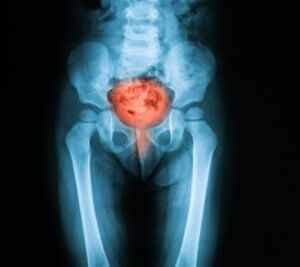

Опромінення при раку

Причина розвитку даного побічного ефекту також може полягати в тому, що організм не реагує адекватно на опромінення. З-за цього відбувається пошкодження тканин сечовивідної системи, що і призводить до захворювання. Нерідко побічні ефекти при лікуванні онкології виникають із-за неправильного дозування променевої терапії.

В цілому, причина розвитку променевого циститу полягає у впливі на органи сечовидільної системи радіаційного випромінювання, за допомогою якого лікують злоякісні новоутворення.